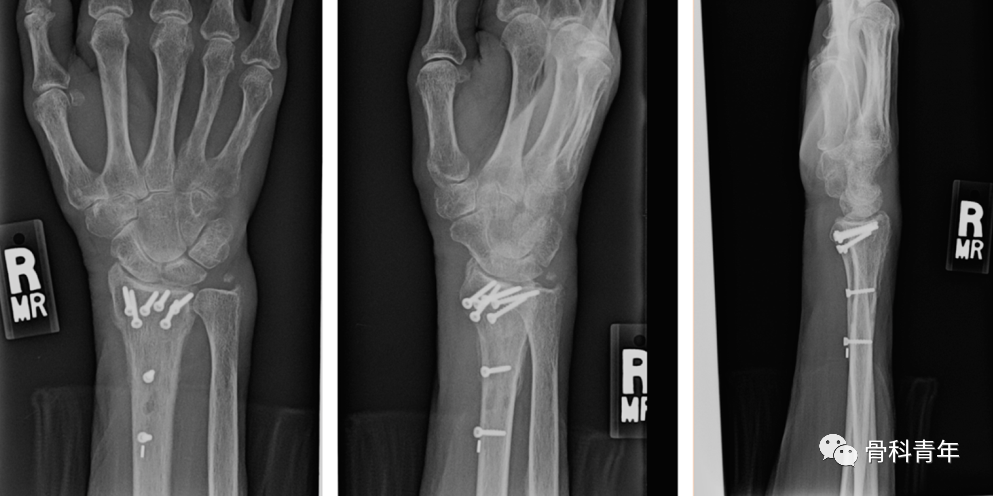

掌侧锁定加压接骨板(Volar locking compression plate,LCP)内固定是桡骨远端骨折治疗的金标准,但LCP并非对所有桡骨远端骨折均适用,如桡骨极远端骨折、背侧缘骨折、掌侧die-punch骨折等;同时,LCP钢板也具有一定的并发症发生率,包括旋前方肌损伤、骨折血运破坏、掌侧软组织激惹、背侧肌腱磨损等,同时对严重骨质疏松患者存在较高的内固定失效风险。

髓内钉技术广泛应用于长骨骨干骨折,闭合或有限切开复位有效降低医源性因素对血运的破坏,并具有良好的轴心固定生物学优势。桡骨远端髓内钉出现较晚,该技术适用于完全关节外骨折及简单的关节内骨折,对关节内粉碎骨折并不适用。